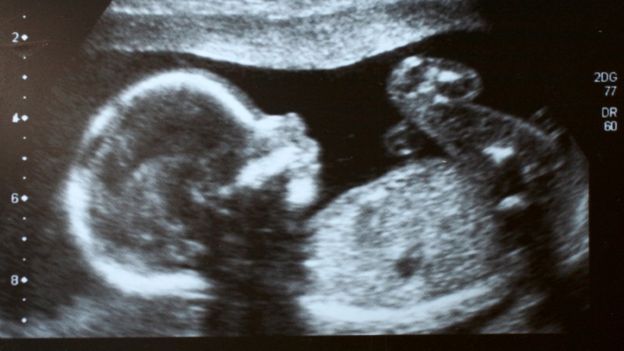

Por ello es que los médicos que atendieron a Mónica Vega en Barranquilla, Colombia, quedaron sorprendidos. Al realizarle una ecografía durante su séptimo mes de embarazo, se percataron de que dentro de su vientre se gestaba una bebé en cuyo abdomen había un feto más pequeño, con su propio cordón umbilical y rodeado de líquido amniótico. Usualmente el gemelo parásito es descubierto en una etapa posterior al embarazo e, incluso, años más tarde puede ser confundido con un tumor. De modo que el caso de Mónica Vega y su bebé, Itzamara, es único, pues los médicos lograron identificar al fetus in fetu previo al alumbramiento de la mujer. Según explicó el cirujano Miguel Parra a un programa de la cadena Caracol, se tomó la decisión de adelantar la cesárea de Vega en la semana 37 del embarazo, para posteriormente intervenir a Itzamara, a la que se le extrajo el gemelo parásito.

Parra detalló que no era posible esperar a la semana 40, pues el pequeño feto dentro de Itzamara continuaba creciendo y podía convertirse en una amenaza para su salud. Los médicos explicaron que el fetus in fetu contaba con extremidades, pero carecía de corazón y cerebro, por lo que su vida dependía por completo de la de Itzamara.

'Fetus in fetu': la explicación En casi el 100 por ciento de los casos, las células que formarán a gemelos idénticos se dividen durante la primera semana de gestación. Cuando este proceso ocurre en la segunda semana, los bebés podrían desarrollarse como siameses. En el caso ocurrido en Barranquilla, la división de células tuvo lugar hasta el día 17, por lo que "dos bebés se formaron no de manera simétrica, eso produjo un bebé que está dentro de su hermano embarazado", según explicó Parra el programa 'Los informantes'.